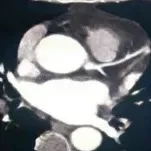

之后患者完善了冠脉CT及动态心肌SPECT检查。冠脉CT示:左前降支近段30%~50%狭窄,其余心外膜冠状动脉未见明显病变,同时可见到从心尖至侧壁的显著肌小梁化(图2)。患者SPECT回报:运动相左室显影清晰,左心扩大、部分下壁近心尖处见放射性缺损区,LVEF值36%;静息相与运动相比较,部分下壁近心尖处未见明显填充,呈不可逆性缺损,LVEF值35%。

图2. 冠脉CT结果